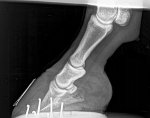

The x rays have been sent over to me. These are her front feet.

Wow that pedal bone is so close to the sole.... the toes are very long - even a trim to shorten the toe will help but a whole resection is completely unneccessary. Have you called a podiatrist?

she is due her trim this week. I don’t mean to come across rude now I’m genuinely intrigued, (it’s hard to tell tone over the internet!)when you say it’s unnecessary why would a vet suggest this? I feel like if they take the shoe off they may find more that they’re hoping to with that pedal bone. I do wonder how this resection even works, I know it relieves the pressure but how can this kind of rotation be rectified with such a procedure? The vet explained it’s the pressure releasing and then she’ll be in less pain thus being able to heal better but for me that bone is so far rotated I can’t see a way back

hooves grow, so if you manage to resolve the cause of the laminitis you can grow a tighter connection back down and the pedal bone has the potential to end up back where it should be.

The trouble being that hooves take a fair time to grow, and sometimes don't always grow in helpful directions.